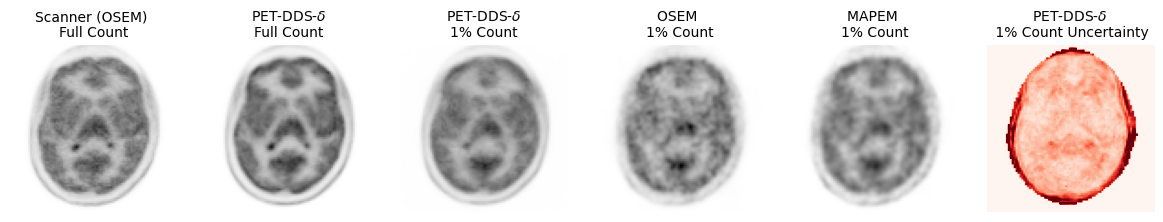

Figure 1: Example transverse slices from 3D images reconstructed from a test dataset. The uncertainty image (far-right) is a preliminary result from sampling the posterior by repeating 25 randomly-seeded PET-DDS-δ\delta reconstructions, and calculating the voxel-wise coefficient of variation.

Table I shows that PET-DDS-δ\delta of the 1 % data more closely matches the full-count reconstruction, achieving lower NRMSE values compared to the baseline methods as expected. This analysis is supported qualitatively by Figure 1, in which PET-DDS-δ\delta retains higher visual fidelity compared to the other low-count reconstructions. In our bias-variance analysis in Figure 2, we see that the reduced NRMSE values are primarily due to reduced variance with respect to the Poisson noise realisations, with a higher minimum bias observed for PET-DDS-δ\delta than for MAP-EM.